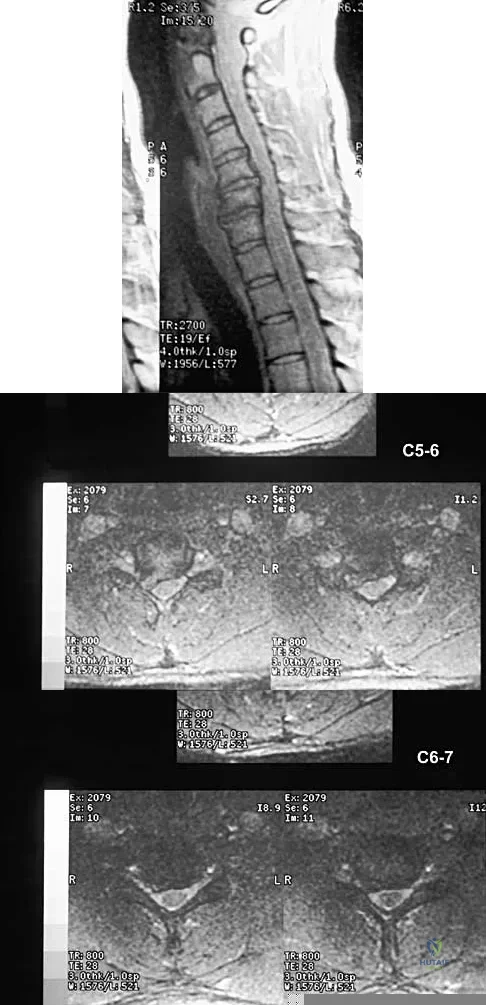

Question 32:

A right-handed 14-year-old pitcher has had a 3-month history of shoulder pain while pitching. Examination reveals full range of motion, a mildly positive impingement sign, pain with rotational movement, and no instability. Plain AP radiographs of both shoulders are shown in Figures 25a and 25b. Management should consist of

Correct Answer: rest until symptoms have resolved, followed by a gradual return to pitching.

The patient has the classic signs of Little Leaguer's shoulder, with findings that include pain localized to the proximal humerus during the act of throwing and radiographic evidence of widening of the proximal humeral physis. Examination usually reveals tenderness to palpation over the proximal humerus, but the presence of any swelling, weakness, atrophy, or loss of motion is unlikely. The treatment of choice is rest from throwing for at least 3 months, followed by a gradual return to pitching once the shoulder is asymptomatic. Carson WG Jr, Gasser SI: Little Leaguer's shoulder: A report of 23 cases. Am J Sports Med 1998;26:575-580.

Barnett LS: Little League shoulder syndrome: Proximal humeral epiphyseolysis in adolescent baseball pitchers. A case report. J Bone Joint Surg Am 1985;67:495-496.